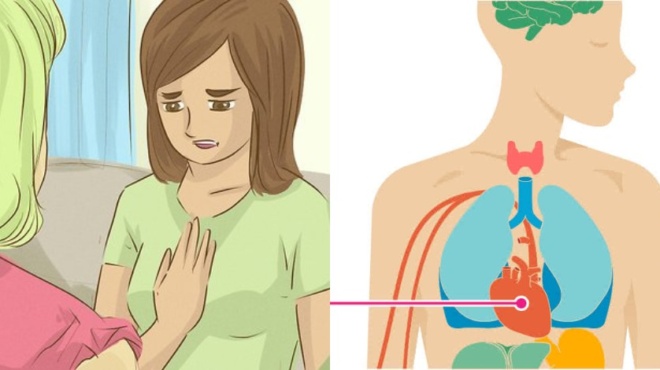

Περίπου 1,7 εκατομμύρια περιπτώσεις εγκεφαλικού τραυματισμού συμβαίνουν στις ΗΠΑ κάθε χρόνο. Περίπου 5,3 εκατομμύρια άνθρωποι ζουν με αναπηρία που προκαλείται από αυτό το τραυματισμό. Κανείς δεν έχει συμβουλές που μπορεί να σας προστατεύσουν 100%, αλλά οι γνώσεις μας μπορούν να σας βοηθήσουν να αποφύγετε σοβαρά προβλήματα μετά από μια διάσειση και να λάβετε όλα τα απαραίτητα μέτρα για να την αντιμετωπίσετε.

Εμείς εκτιμάμε την υγεία και θέλουμε να μοιραστούμε μερικά σημαντικά συμπτώματα που θα μπορούσαν να υποδηλώνουν ότι μπορεί να έχετε μια διάσειση.